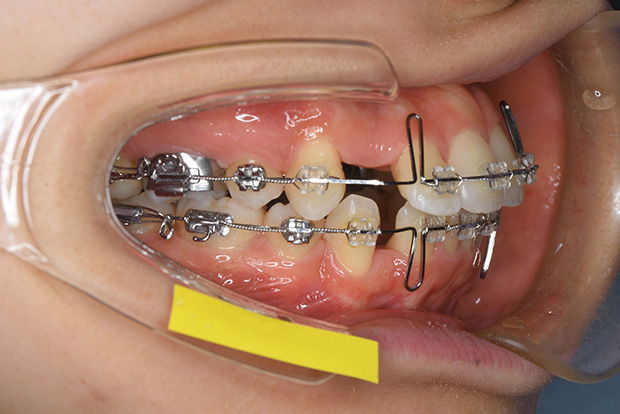

【ハーフリンガル】叢生 抜歯 上顎舌側マルチブラケット装置

| 主訴 |

ガタガタ |

||

|---|---|---|---|

| 診断名 |

右側Angle II級叢生 |

||

| 年齢 | 19歳 | 性別 | 女性 |

| 治療に用 いた装置 |

ハーフリンガル装置 (セミカスタム) | 抜歯部位 | 上顎両側第一小臼歯 下顎両側第二小臼歯 |

| 治療期間 ・回数 |

2年・24回 | 治療費 概算 |

約85万円 (調整料を含む) |

| 治療内容 詳細 |

歯科衛生科に入学し、自分の歯ならびが気になり始めたとのこと。上の歯列のみ舌側矯正(裏側矯正)、下は表側の、ハーフリンガルで治療を行いました。 |

||

| リスク・ 副作用 |

装置による違和感。疼痛、歯根吸収など |

||